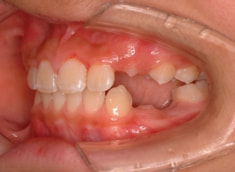

治療開始時

治療開始から約3ヶ月後